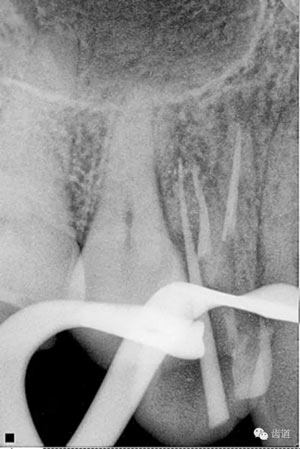

數(shù)碼x攝影顯示:近中頰根及腭根根管充填恰填,遠(yuǎn)中根管有遺漏。

顯微鏡下反復(fù)探查根管,未探及遺漏根管口,放置棉球,zoe暫封。轉(zhuǎn)診上級醫(yī)生處理。